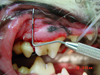

During the dental exam, your veterinarian examines the teeth and overall condition of your pet’s mouth. They examine the surface structure of your pet’s teeth looking for evidence of surface abnormalities (such as enamel fractures, defects and discoloration), displacement of teeth, missing or extra teeth, and cavities. Inflammation and/or discoloration of the gums also indicate present problems. The vet uses a periodontal probe to measure for periodontal pockets around teeth and looks for evidence of conditions that may lie below the gum line that may require further investigation and treatment.